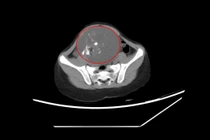

Các bác sĩ Bệnh viện Đa khoa tỉnh Quảng Ninh vừa qua đã thực hiện phẫu thuật bóc tách khối u quái thành công cho bệnh nhi T.N (6 tuổi) ở TP Hạ Long. Theo gia đình cho biết, gần đây cháu N. ở nhà thường xuyên táo bón, khó đại tiện, thỉnh thoảng thấy bụng có khối cứng khi đói nên đưa đến Bệnh viện Đa khoa tỉnh thăm khám.

Qua siêu âm và chụp cắt lớp vi tính, bác sĩ phát hiện khối u kích thước vùng hạ vị kích thước lớn, ít di động, ấn gây đau tức. Bệnh nhi được chẩn đoán u buồng trứng và chỉ định phẫu thuật cắt u.